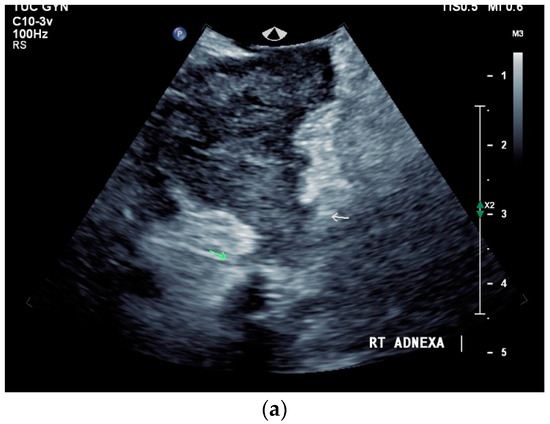

What can be seen sonographically? Ascites can be either diffuse or focal type [Figure 1a,b]. Due to the protein and cell content, these tend to be echogenic, rather than non-echoic. Attention must be paid to enlarged lymph nodes at the same time. Any thickening of the peritoneum and mesentery must be specifically searched for. This also applies to macronodular changes in the peritoneum and mesentery [Figure 1c–h]. The smallest speck-like deposits are usually not visible on ultrasound [36]. With ascites, it may be possible to observe the adhesions [31,37]. Kumar et al. were able to histologically detect granulomatous inflammation in 17/19 (89%) patients using ultrasound-guided needle biopsy of omental thickenings. In a country like India, the authors interpreted this as a manifestation of tuberculosis [32].

Figure 1.

Typical changes in the peritoneum, mesentery, and omentum in patients with tuberculosis. Ascites with pronounced septa (a). Ascites encapsulated between the abdominal wall and colon (b). Omental thickening with non-echoic caseous abscesses and few echogenic contents (c); hypoechoic nodules in hyperechoic thickened peritoneum (d). Significantly thickened hyperechoic peritoneum in B-mode US (right side of image) (marked with arrows). In CEUS, the thickened peritoneum is contrast enhanced in the arterial phase (e). In the parenchymal phase, it shows a decrease in enhancement (f). The thickened hyperechoic peritoneum shows a non-echoic lesion (arrow) (g). In the CEUS, this is not enhanced and instead shows a hyperenhanced rim. This corresponds to caseous necrosis (h).